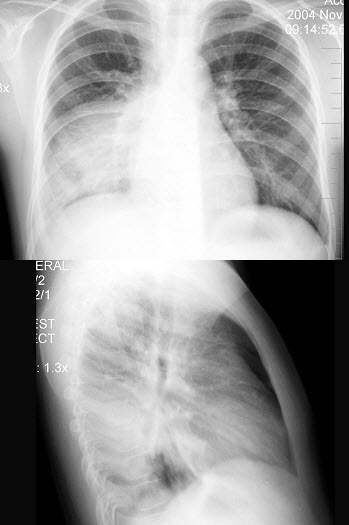

17、单项选择题

女,6岁半,咳嗽发热3天,体温39℃,胸片如图,最可能的诊断是()

A.右肺细菌性炎症

B.右肺结核

C.右侧胸腔积液

D.右肺脓肿

E.右下肺不张